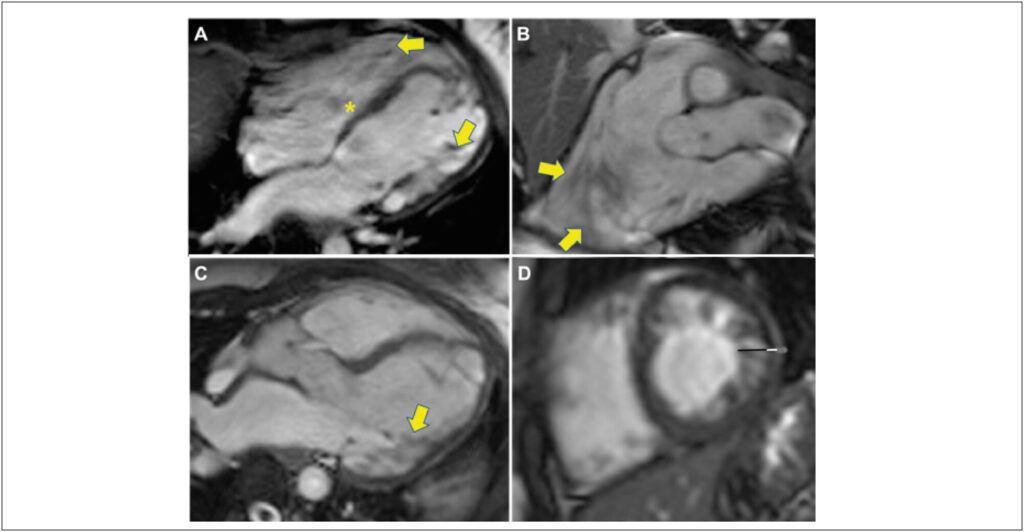

Mulher, 29 anos, com diagnóstico prévio de anomalia de Ebstein, foi encaminhada à ressonância magnética do coração em virtude de dispneia aos esforços com piora progressiva.

As imagens de ressonância magnética cardíaca (Siemens Essenza 1,5T) demonstram dilatação atrial direita e implante baixo do folheto septal da valva tricúspide. Adicionalmente, observam-se aumento da trabeculação ventricular esquerda, característica da não compactação miocárdica, e sinais de restrição do folheto mitral posterior, secundário à provável doença valvar reumática.